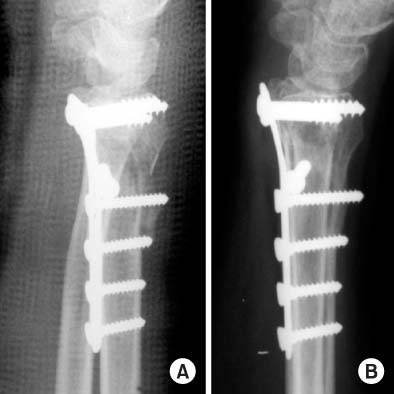

Fig. 2

(A) The distal radius fracture was fixed with conventional plate, and the volar tilt was acceptable immediately after operation.

(B) At 3 months follow-up, the union is advanced with collapsed dorsal cortex.

Fig. 2 (A) The distal radius fracture was fixed with conventional plate, and the volar tilt was acceptable immediately after operation. (B) At 3 months follow-up, the union is advanced with collapsed dorsal cortex.